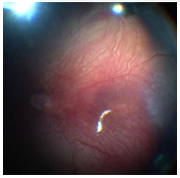

ETAPA 3:

Se caracteriza por la presencia de tejido proliferativo fibrovascular

extra-retinal que se proyecta desde el borde posterior del ridge

hacia el vítreo, o sobre el plano de la retina (Foto C).

Inicialmente se observan pequeñas yemas neovasculares (Foto

A) que originarán vasos sanguineos (Foto B). La etapa 3 se

puede subclasificar en leve, moderado y severa dependiendo de la

extensión de tejido fibrovascular extraretinal que infiltra

el vítreo.